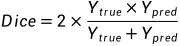

四、评价指标

赛会官方给出了两个评价指标,dice分数和豪斯多夫距离。其中,Dice分数比豪斯多夫距离更重要。

公式为: